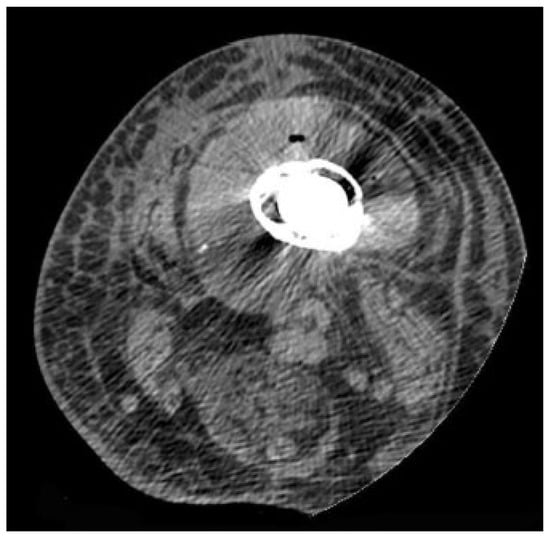

4.3. Computed Tomography